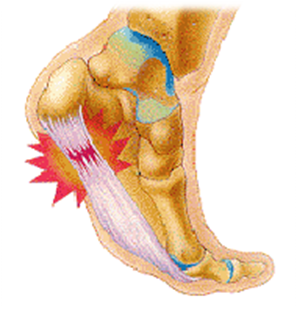

Espolón calcáneo

Una causa frecuente de dolor de talón es el espolón, un crecimiento óseo en la parte inferior del hueso del talón. El espolón, visible con rayos X, aparece como una prolongación que puede extenderse hasta 1 ó 2 cms. Cuando no hay indicación de crecimiento del hueso, a veces se llama a esta condición "síndrome de espolón del talón".

Los espolones resultan de un esfuerzo excesivo de los músculos y ligamentos del pie, que estira la banda de tejido que conecta el talón y la parte anterior del pie, y arranca repetidamente la membrana que cubre el hueso del talón. Esta condición puede ser resultado de un desequilibrio biomecánico, de correr, de zapatos inapropiados o demasiado gastados, o de obesidad.

Esta lesión suele tratarse con éxito mediante el uso de plantillas ortopédicas que alivian la tensión sobre la zona haciendo que los movimientos sean menos dolorosos. Los ejercicios de estiramientos también son efectivos para eliminar o disminuir el dolor. En caso de que aparezcan inflamaciones, se pueden tratar mediante infiltraciones de fármacos antiinflamatorios.